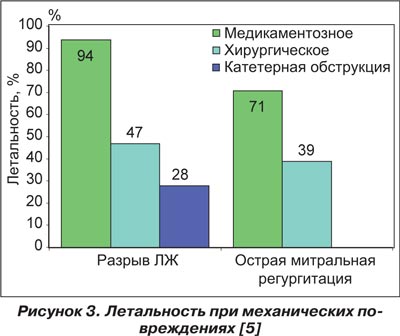

Самым большим этапом в уменьшении смертности при кардиогенном шоке, связанным с разрывом миокарда, было внедрение оперативных вмешательств по устранению механического дефекта, нанесенного некрозом миокарда. Коррекция митральной регургитации при отрыве хорд клапанного аппарата путем ушивания хорды или протезирования клапана, ушивание или постановка обтураторов на место дефекта межжелудочковой перегородки значительно увеличили выживаемость больных с разрывами миокарда (рис. 3). Хирургическое лечение механических дефектов, возникающих при остром инфаркте миокарда, уменьшило внутригоспитальную летальность почти в два раза (рис. 3).

Если вспомнить статистику госпитального периода больных острым инфарктом, осложненным кардиогенным шоком по причине разрыва миокарда, то внутригоспитальная летальность при медикаментозной терапии этой категории больных составляет 94 % в самых развитых странах. Правильно выбранная тактика медикаментозной коррекции, своевременная диагностика механического осложнения инфаркта миокарда и оперативное лечение подарили больной новую жизнь.